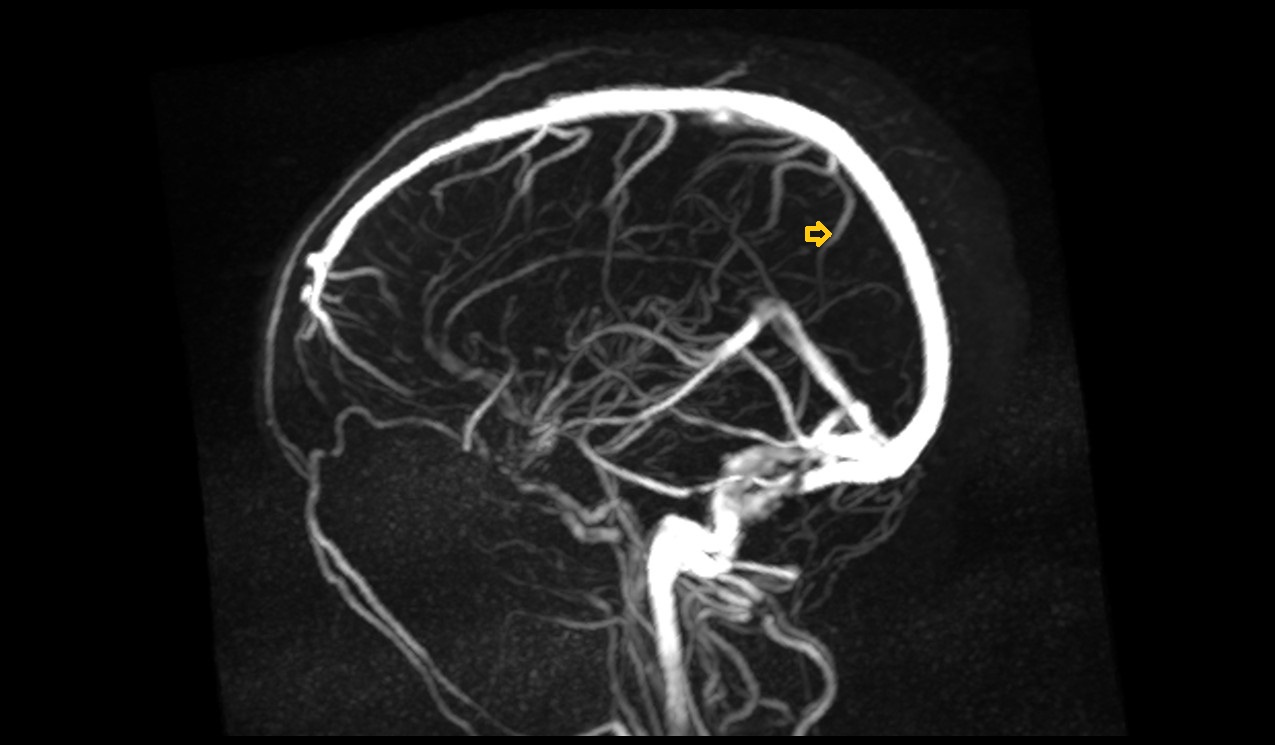

- Superior sagittal sinus

- Confluence of sinuses

- Straight sinus

- Inferior sagittal sinus

- Transverse sinus

- Sigmoid sinus